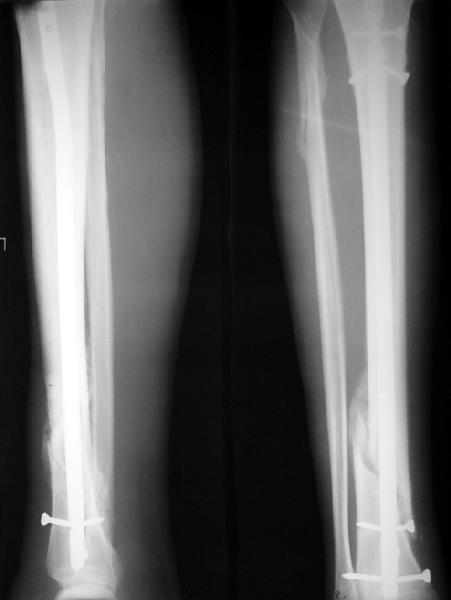

На мой взгляд, на снимках, приведённых Вами - неправильно сростающийся перелом дистальной трети большеберцовой кости, состояние после остеосинтеза интрамедуллярным гвоздём.

Как Вы пишите снимок под номером 1 - менсяц после операции, под номером 2- два месяца после операции.

Вы не послали послеоперационный снимок, поэтому трудно судить о состоянии редукции после операции.

I think that the X-Rays show S/P IMN of Spiral # of the Distal Tibia consoles in misalignment.

You wrote that a picture number 1 - f month after the surgery, and number 2-two months after the surgery.

You have not sent a postoperative X-Rays; so it's impossible to discuss about the condition of a reduction after operation.